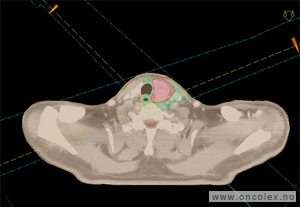

Ved ultralydundersøkelse føres en ultralydprobe inn i skjeden.